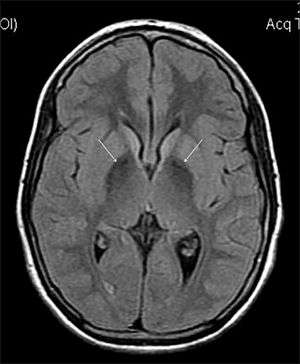

MRI hypointensity (white arrows) in the globus pallidi that indicates the presence of iron deficiencies which would be seen in a diagnosis of Aceruloplasminemia | |

Diagnosis of this disorder depends on blood tests demonstrating the absence of serum ceruloplasmin, combined with low serum copper concentration, low serum iron concentration, high serum ferritin concentration, or increased hepatic iron concentration. MRI scans can also confirm a diagnosis; abnormal low intensities can indicate iron accumulation in the brain.[4]